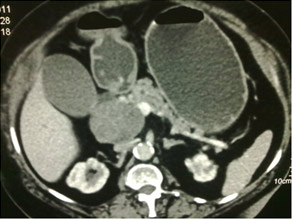

CT Scan of Infected Pancreatic necrosis